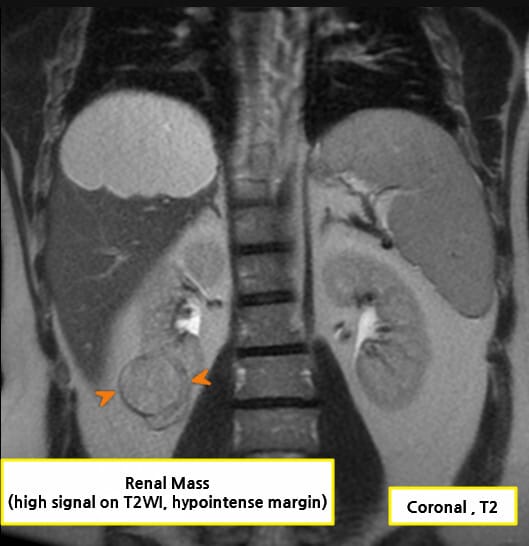

| 🔵 MRI |

| 조영제 금기 환자에서 사용하며, 정맥 침범 및 신정맥혈전(thrombus) 확인에 유용합니다. |

영상소견 정리

CT/ MRI 소견

조영증강 영상에서 고형성 종괴 + 중심 괴사, 혈관 침범

| CT/ MRI 소견 |

| ✅ 조영증강 고형 종괴 |

| CT에서 조영제 주입 시 병변이 비정상적으로 밝게 조영되며, 실질보다 높은 밀도 |

| ✅ 중심 괴사(necrosis) |

| 종양이 자라면서 내부 혈류 공급이 떨어져 중심부 괴사가 흔하게 발견. |

| ✅ 신정맥, 하대정맥 침범 |

| 정맥 내 종양 혈전이 관찰되며, 이는 병기와 치료 방침에 결정적 영향을 미칩니다. |